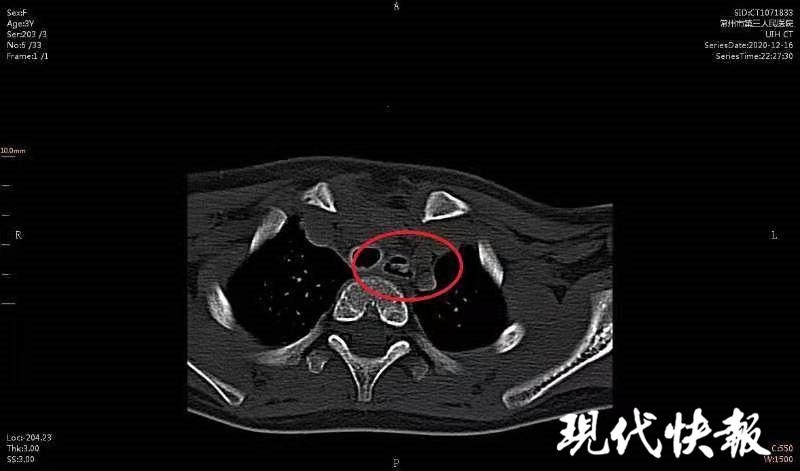

△CT顯示女童食道內(nèi)有異物